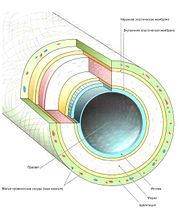

| 11:40, 19 июля 2016 | Mishci sport68.jpg (файл) |  |

42 КБ | Anes | Послойное строение стенки кровеносного сосуда | 1 |